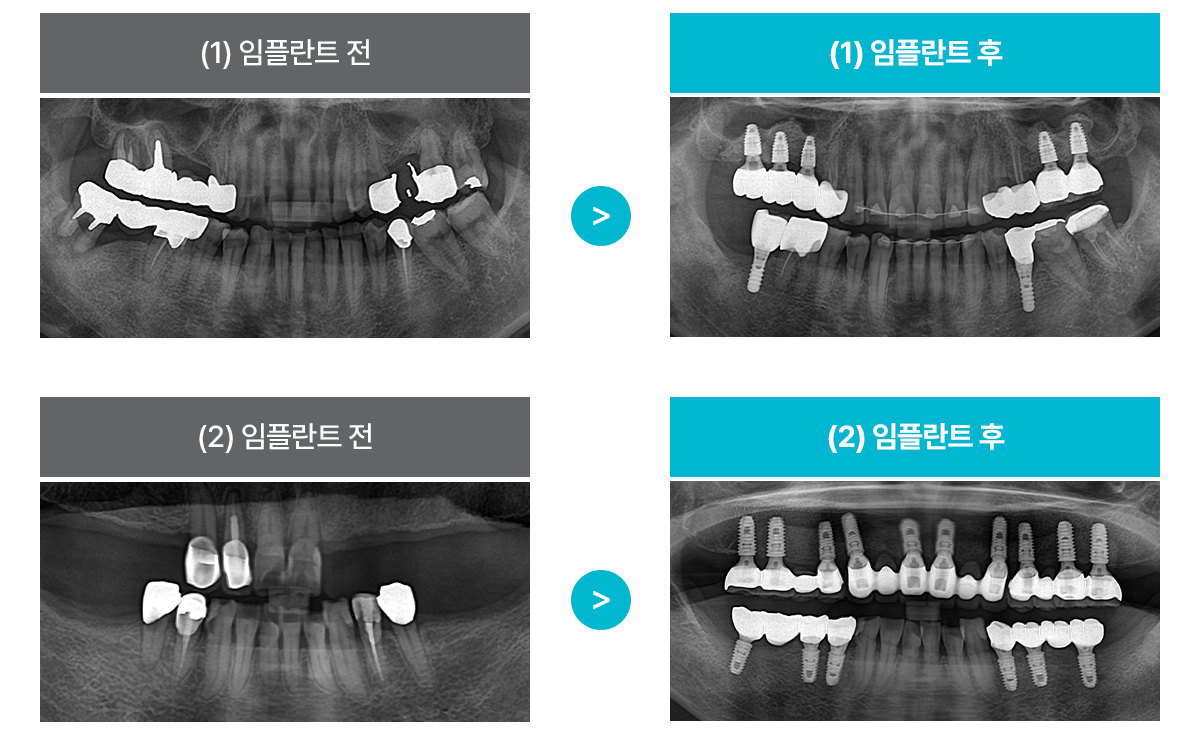

ÀÓÇöõÆ® Ä¡·á »ç·Ê